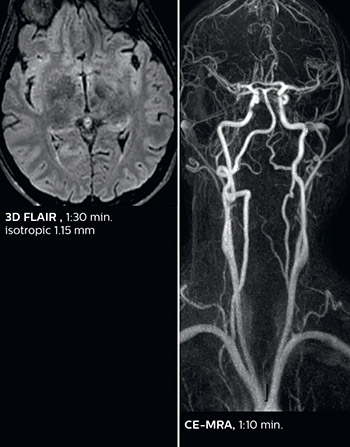

Fast MS protocol with optional sequences

The abbreviated MS protocol for brain is only around 9 minutes, so in case of suspected multiple sclerosis, one or two more advanced sequences may be added, such as PSIR (phase sensitive inversion recovery) or susceptibility-weighted sequences to help us make more confident diagnoses in these inflammatory cases.

In this example, the optional 3D multishot susceptibility weighted sequence with 0.6 mm isotropic voxels is 2 lesions with a central vein sign (arrows) and one lesion with a phase-rim sign (arrowhead). The total scan time, including SmartBrain and axial PD/T2 3mm, is 11:10 min. and is 18:30 min. with the optional 3D PSIR and 3D SWI multishot included.

3D TFE T1

3D FLAIR

DWI image

3D T1w TSE Gd

3D PSIR

3D SWI